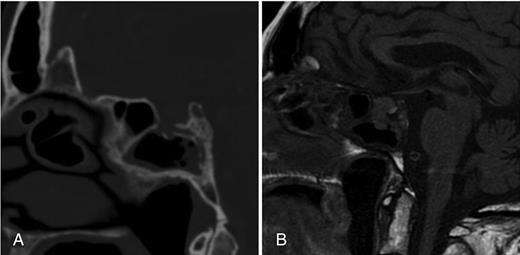

MRI performed 3 weeks after initial presentation. (A) T2-weighted MRI coronal section displaying an expanding, infiltrative pituitary fossa mass. (B) T1-weighted MRI sagittal view, indicating that the lesion is locally infiltrating the sphenoidal sinus. (C) Post-gadolinium sagittal T1-weighted MRI indicating a heterogeneously enhancing mass.

The patient's headache worsened despite management with simple analgesia. A repeat MRI performed 3 weeks after presentation demonstrated that the lesion had expanded in size and appeared to be breaching the diaphragma sella, with extension to the inferior surface of the optic chiasm (Fig. 2).